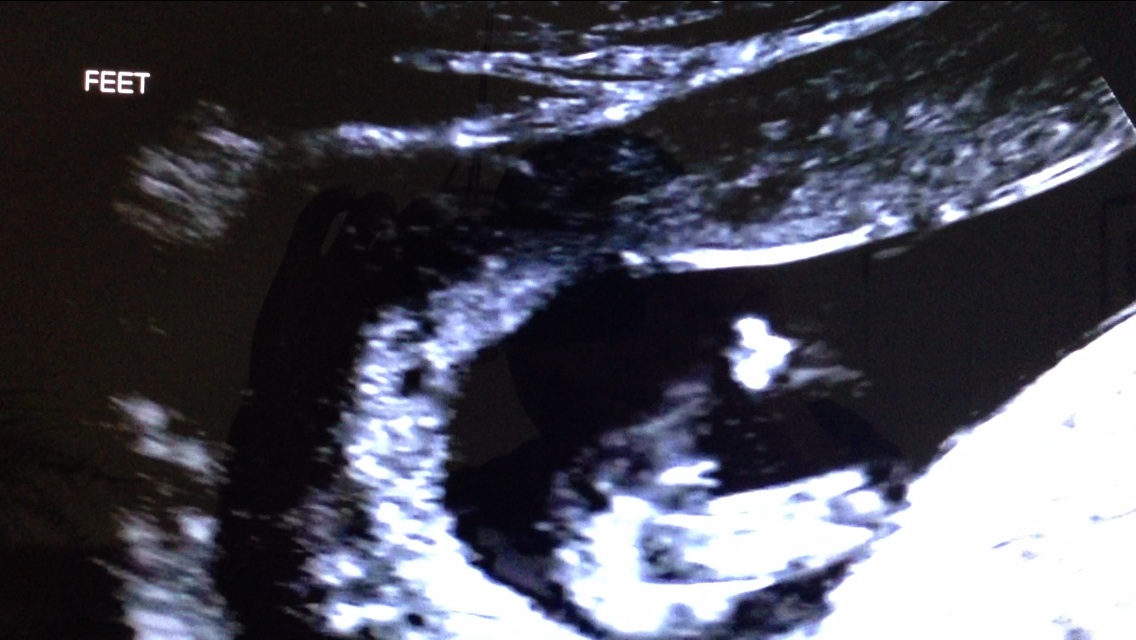

Thank you!! I can't believe I might have a boy in there after 3 girls! Here are two more.. Does anyone see anything girly at all in these?? So hard to not get excited yet :). Attachment 20339

Attachment 20340

I'd be very, very hopeful for blue with these pictures. The nub pics are stacked almost vertical and the potty shot pics, although mighty early, are showing a good deal of parts that look boyish. With both pointing the same direction, I'd be cautiously thinking blue for you :)

Leaning boy